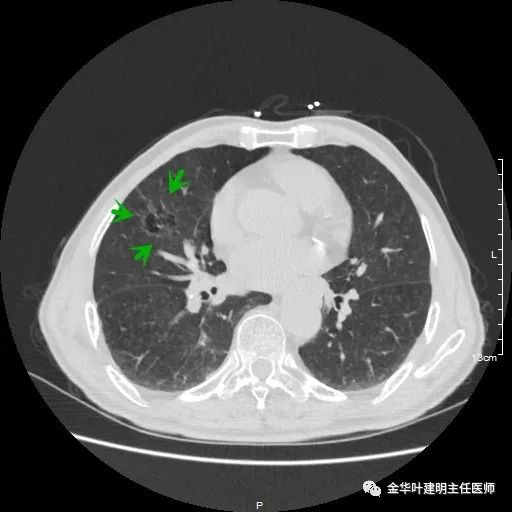

金华的某A,今年已经80岁了,前些天检查发现右下肺部占位,让我会诊。我打开电脑一看图,发现右下肺是典型的实性分叶状的占位,基本可肯定肺癌,余肺仍有多处磨玻璃影及类似慢性炎的病灶,是不是合并炎症?还是多原发肺癌?鉴于其中叶肺门部混合磨玻璃结节边缘略显模糊,为了防止炎性病灶,让其进行了10天的静脉抗炎治疗,但复查靶扫描后发现病灶无任何吸收好转,靶扫描上把细节显示的更清楚了,反而更坚定了我判断其为肺癌的结论。对于这样年纪的多原发癌,我们该如何来进行临床思考呢?治疗该如何建议与决策?当然最后的结果要如实告知患方后,由他们自己决定。

以上示右上病灶,我们称其病灶1。为囊腔型病灶,边缘为磨玻璃影,且轮廓清楚,局部有点状高密度,需考虑为囊腔型肺癌。单纯从单一病灶来看,这样的年纪可以随访或局部切除。

以上示右肺中叶病灶3。是混合磨玻璃结节,位置差,邻近肺门部,无法局部楔形切除,抗炎治疗后靶扫描显示了更清楚的细节,是典型的肺癌影像特征(此处未另提供)。从单病灶来看,需要行右肺中叶切除并清扫淋巴结才能得以治疗。

以上示右中叶病灶4。也是囊腔型病灶,病灶大,囊壁是磨玻璃密度,亦是较为典型的囊腔型肺癌影像。单病灶看,需中叶切除来治疗,因病灶3的存在,中叶切除可同时解决病灶3与病灶4。